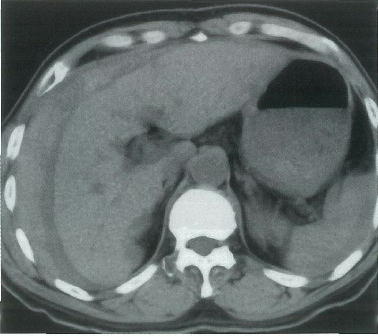

64歳の男性。昨晩から持続する腹痛を主訴に来院した。10年前に肝疾患を指摘された。意識は清明。顔色は不良である。脈拍 112/分,整。血圧 84/60mmHg。血液所見:赤血球 189万,Hb 5.8g/dl,白血球 9600。腹部単純CT(A,B)と造影CT(C,D)とを別に示す。

輸血を開始した後に行うのはどれか。

正解 a

診断 肝癌の腹腔内破裂